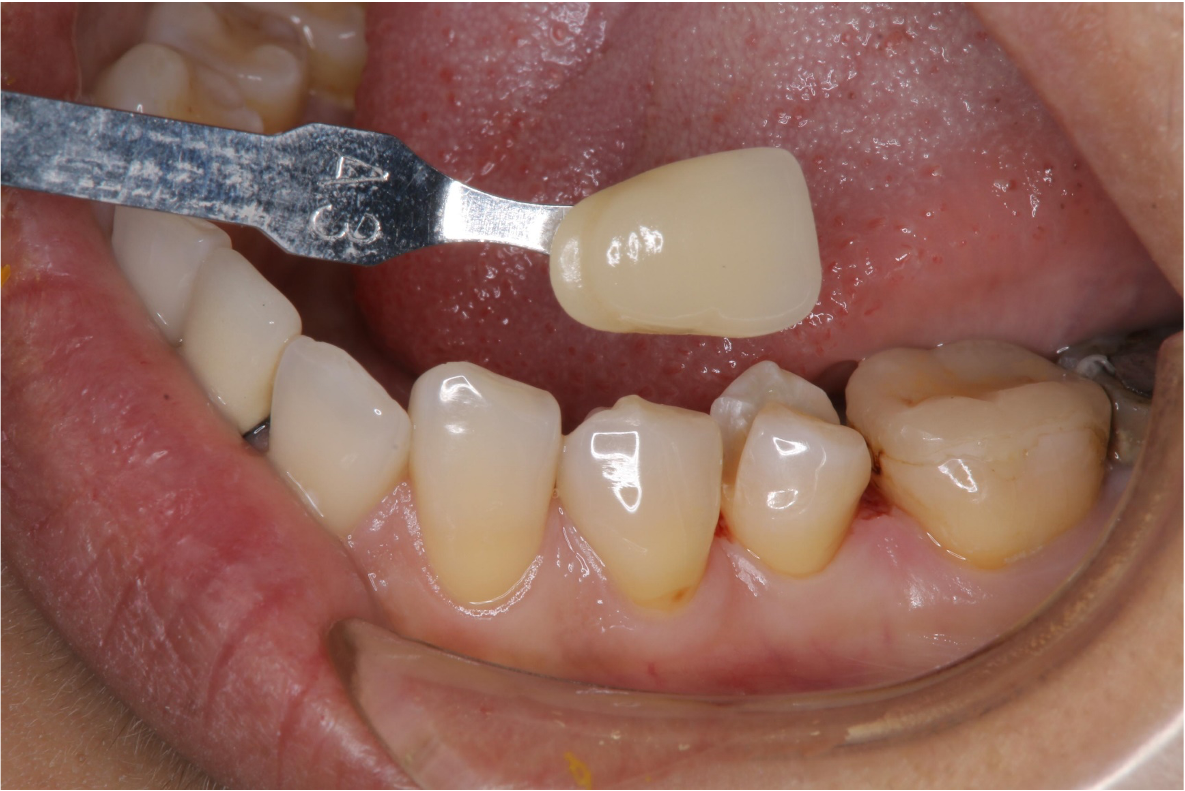

照相比色